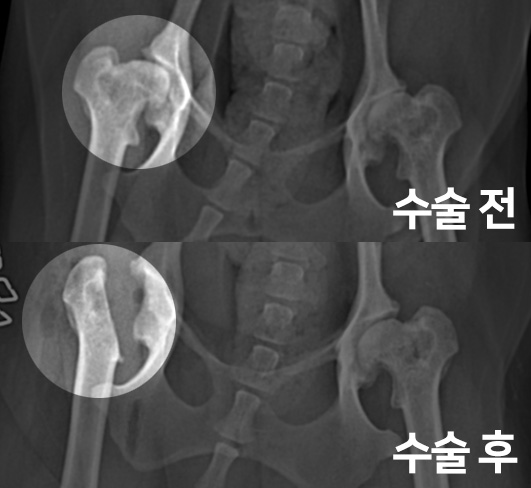

소피는 낙상사고 후 다리를 저는 파행 증상으로 내원하였습니다.

촉진 및 방사선 촬영 결과

대퇴골두 절골술(FHNO)이 필요하다고 판단되었습니다.

문제의 원인이 되는 대퇴골두를 깔끔하게 절단해 주었습니다.

수술 전과 수술 후 촬영한 고관절 방사선 사진입니다.

대퇴골두가 깔끔하게 절단된 것이 확인됩니다.

이제 재활 운동을 통해 체중을 지지할 근육을 키워주게 됩니다.